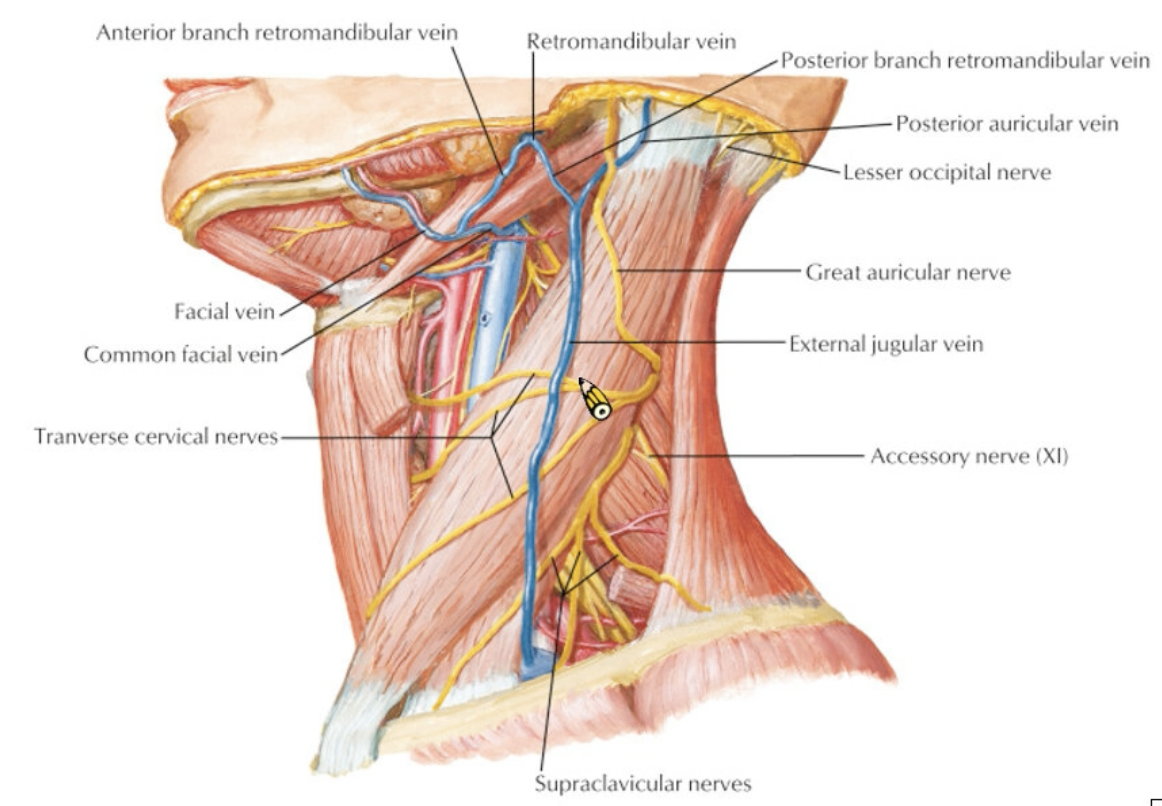

Vein

Info

subclavian vein 在ant. scalene m. 上方